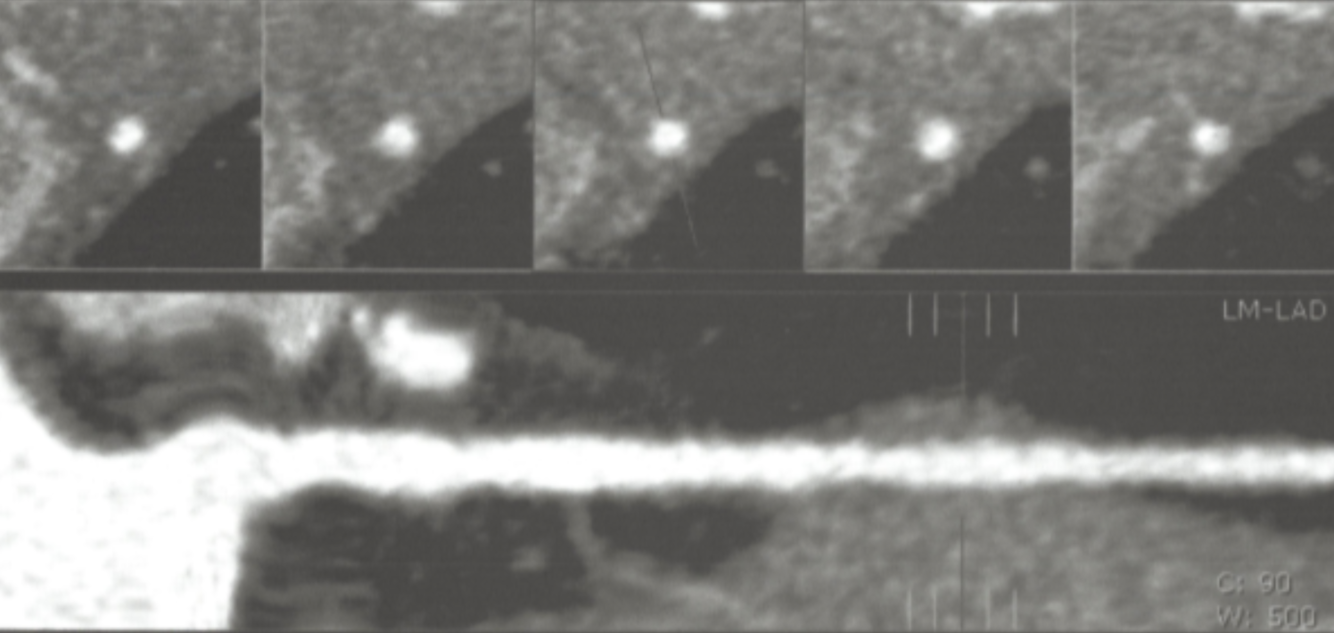

What type of post-processing methods were used to generate the reformatted image shown below?

Multiplanar reformatting and thin slab MIP (5 mm)